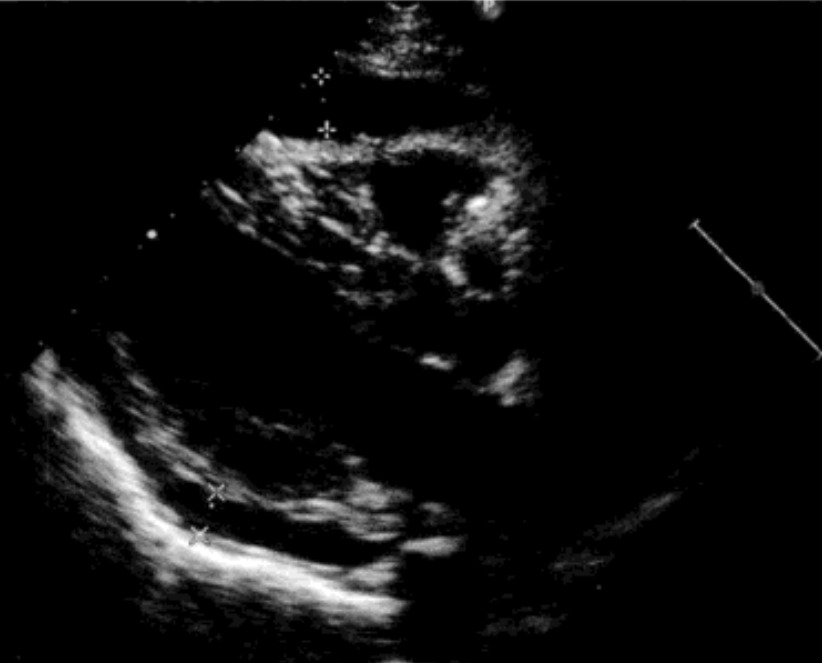

中等量:心脏周围环绕无回声区,左室后壁后方无回声区在1~2cm,右心室前壁无回声区<1cm,液体量在100~500ml。

大量:左室后壁后方无回声区>2cm,液体量>500ml。右室前壁、室间隔及左室后壁呈同向运动,并出现由于心脏自由摆动而出现的摇摆运动。